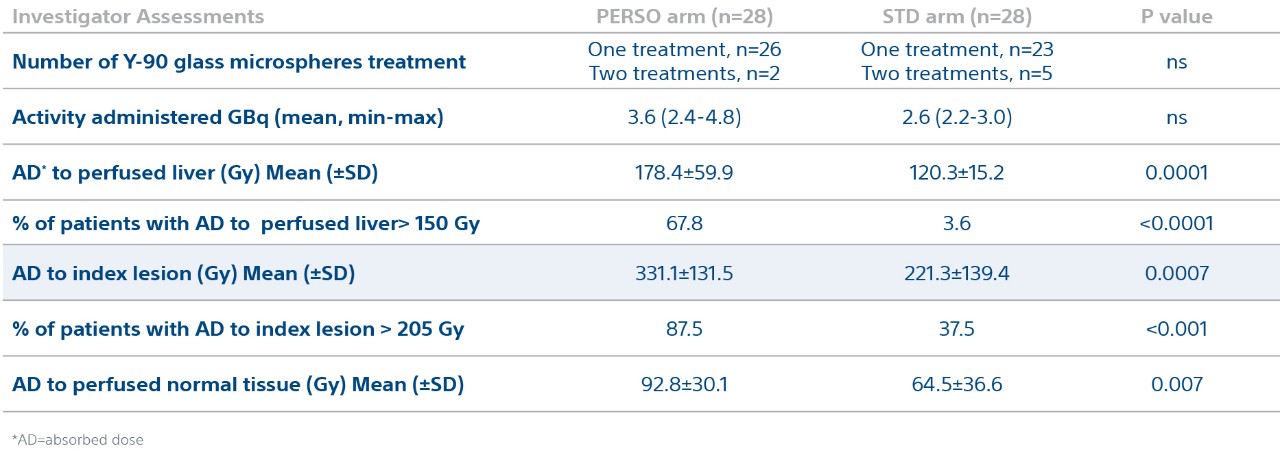

Treatment Characteristics and Dosimetry